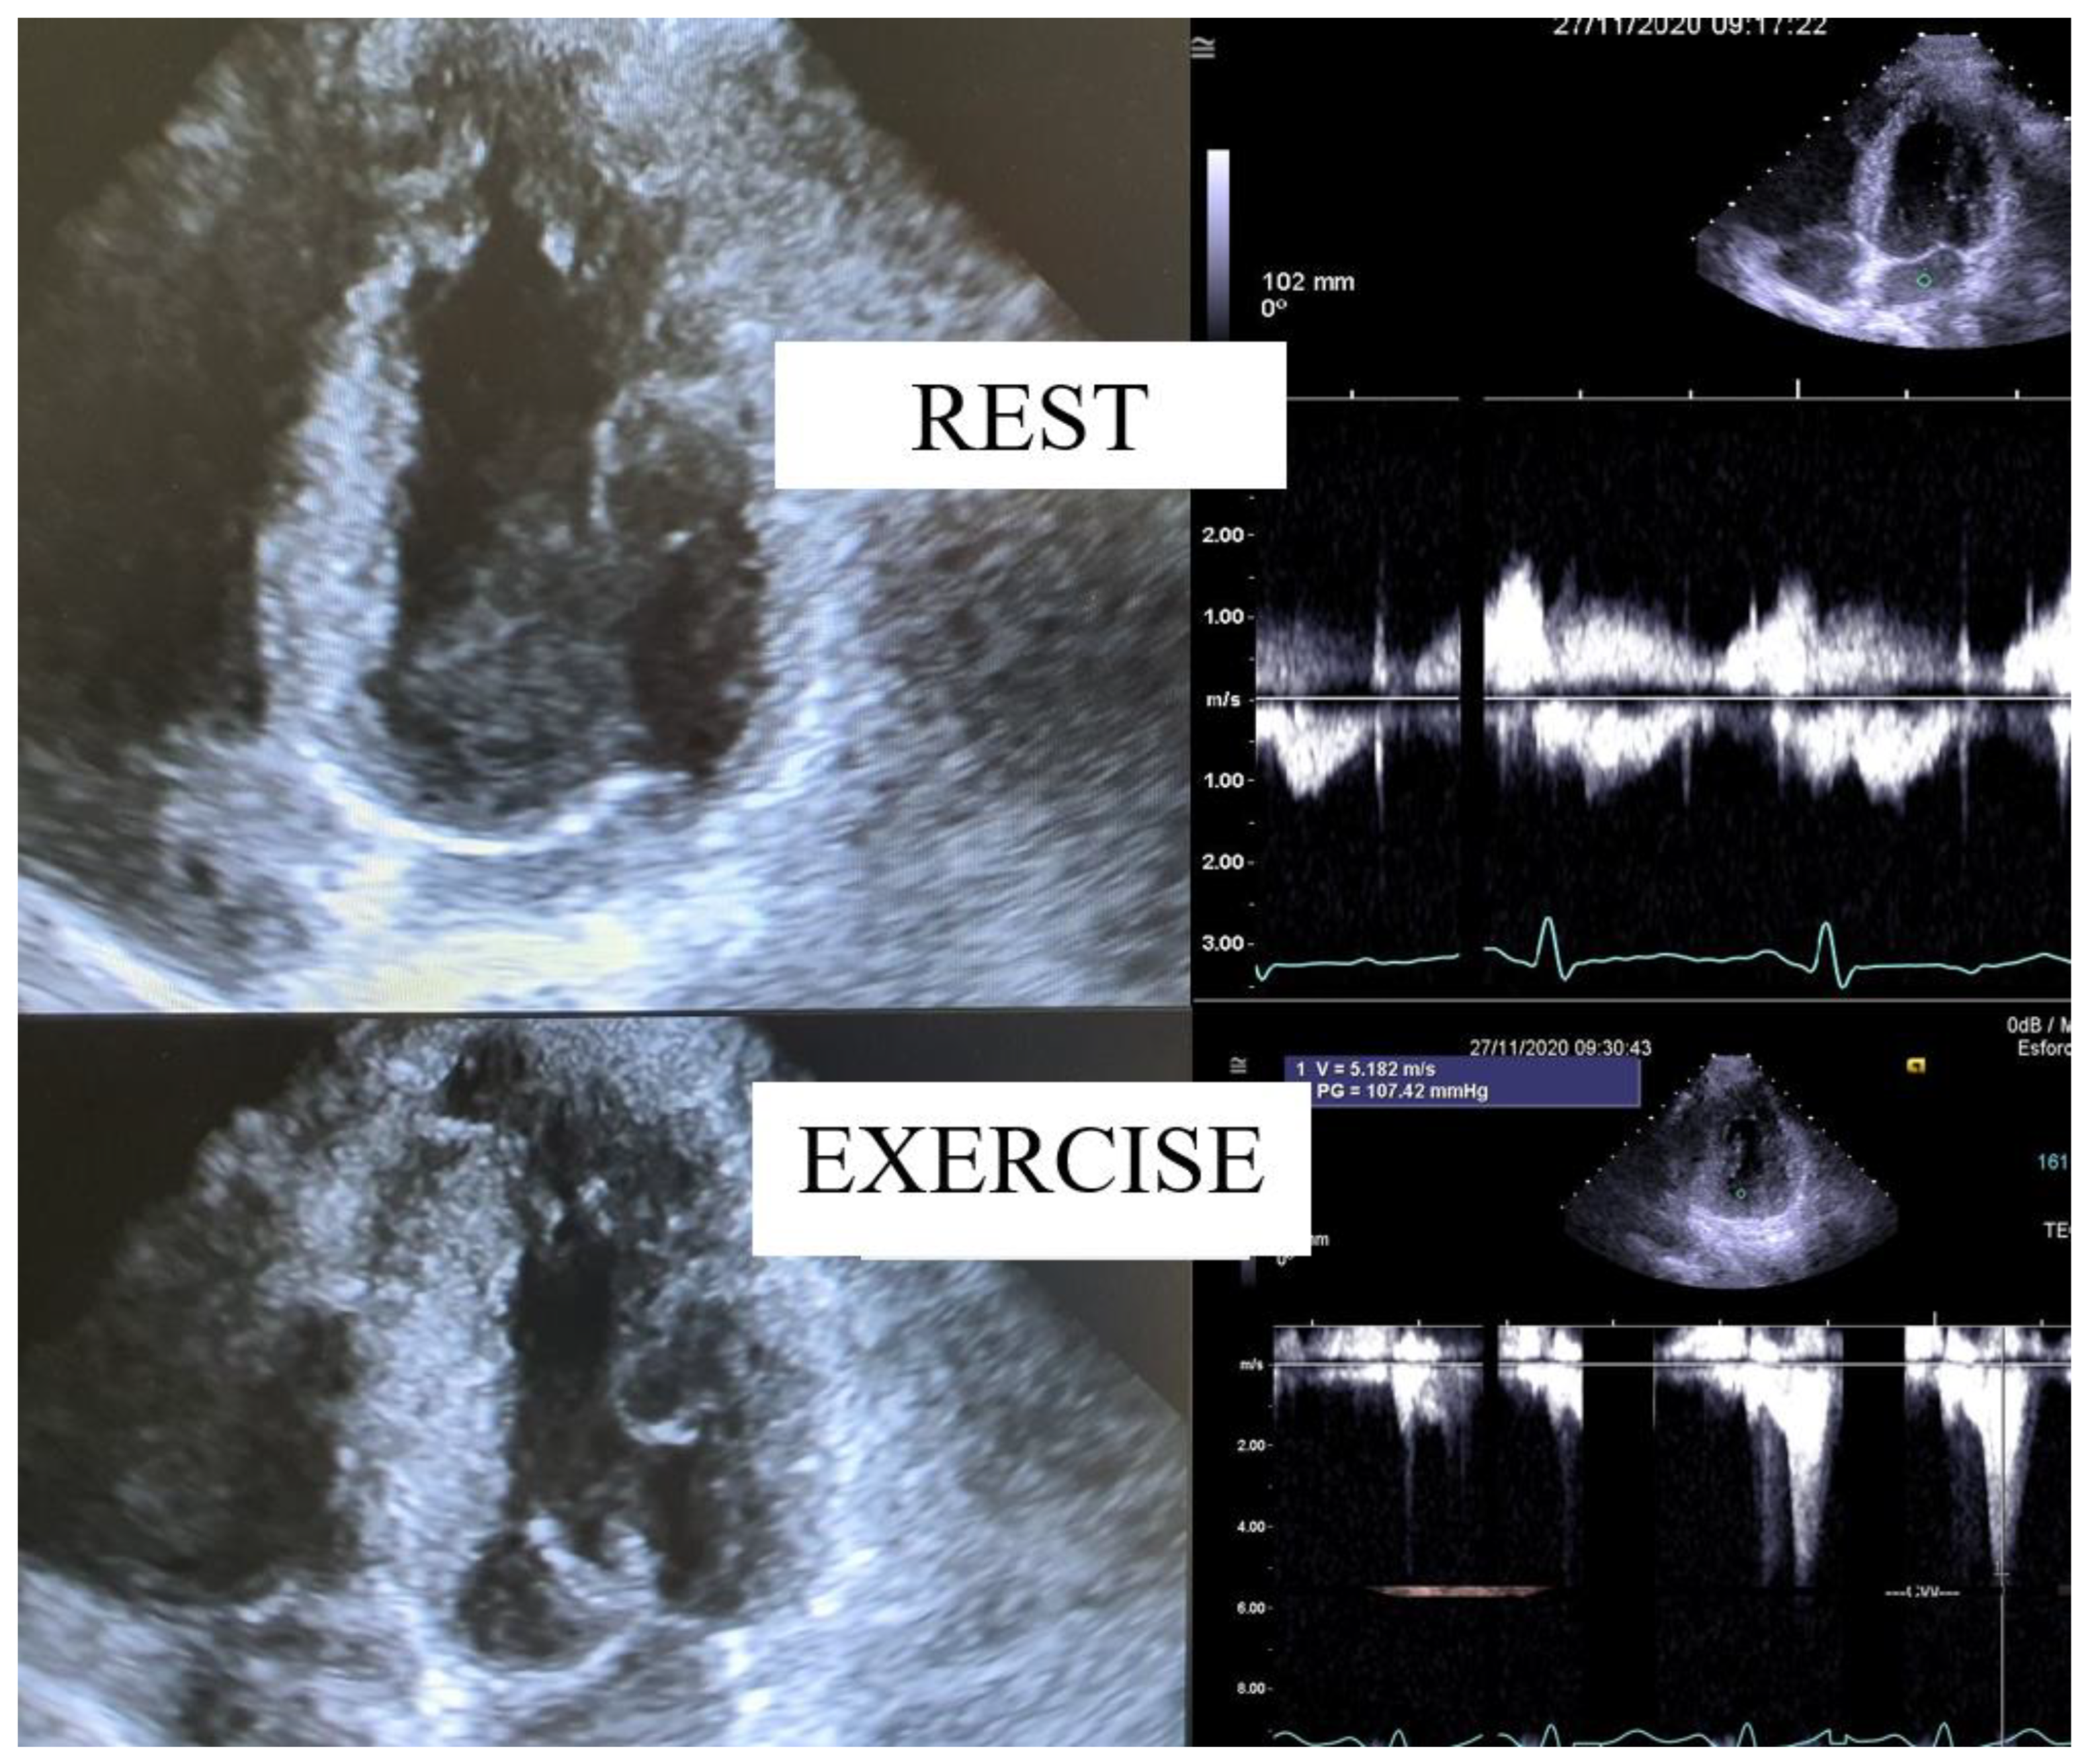

| in [1] | Evaluate IVGs with echocardiography during treadmill exercise and post-exercise in the upright position in patients with HCM. | 17 HCM | Research | Three patients with non-obstructive HCM at rest developed IVGs during exercise. One patient developed this gradient only during orthostatic recovery. The mean IVG in left lateral decubitus (LLD) was 49 ± 4 mm Hg; in orthostatic position it was 62 ± 29 mm Hg (p < 0.001 versus in LLD); at peak exercise it was 83 ± 35 mm Hg (p < 0.001 versus supine rest); during recovery it was 96 ± 35 mm Hg (p < 0.001 versus peak exercise) |

| [27] | As various types of exercise have different consequences on peripheral vascular circulation, this study sought to compare upright treadmill exercise echocardiography (EE) to semi-supine bicycle EE in maximum provoked LVOTO in HCM patients. | 23 HCM | Comparative study | This study demonstrates that, when compared to the semi-supine bicycle EE, the treadmill is better for ascertaining the maximum LVOT gradient in HCM. |

| [40] | The relation between functional capacity and exercise-induced LVOT obstruction in HCM is incompletely defined. The time course of the provoked gradients and the relation to exercise performance were assessed. | 74 HCM | Research | In patients with non-obstructive HCM at rest, the earlier onset of LVOT gradients during treadmill exercise was associated with impaired exercise performance. These findings have yielded insights into the determinants of functional impairment in HCM and support the potential value of exercise echocardiography in the clinical evaluation of patients with HCM. |